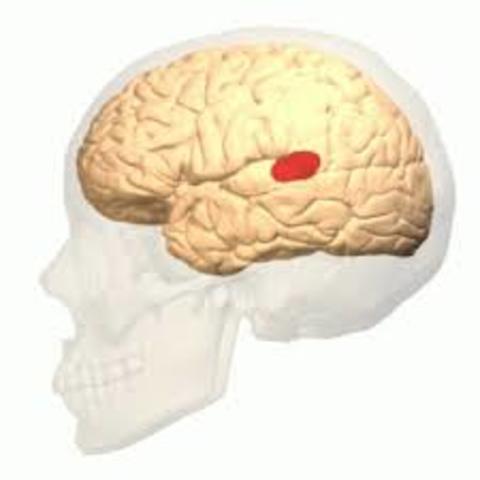

• Paul Broca

Sugirió que la capacidad para hablar podía localizarse en la porción inferior posterior del lóbulo frontal. Broca llamo la atención del mundo científico al señalar que solo el hemisferio izquierdo se alteraba en caso de perdida del lenguaje. Agrego que cuando un paciente perdía el habla, la patología se localizaba en el hemisferio izquierdo, en tanto que las lesiones que afectaban la misma región del hemisferio derecho no producían la perdida de la capacidad lingüística.

Declaro "la afemia se relaciona con lesiones de la tercera circunvolución frontal del hemisferio izquierdo del cerebro"